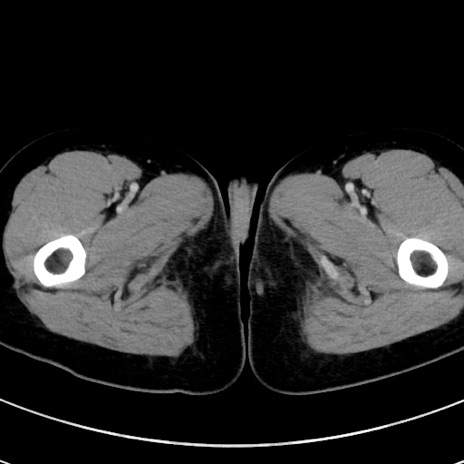

症例17(横断像)

【症例】20歳代女性

【主訴】嘔吐、下腹部痛

【現病歴】昨日夕食後に嘔吐し下腹部痛が出現。本日になっても嘔吐持続し改善しないため来院。

【身体所見】意識清明、BT 37.2℃、BP 108/67mmHg、腹部:平坦、やや硬、下腹部正中から右にかけて圧痛あり、反跳痛軽度あり、tapping pain(+)。

【データ】WBC 13600、CRP 14.94